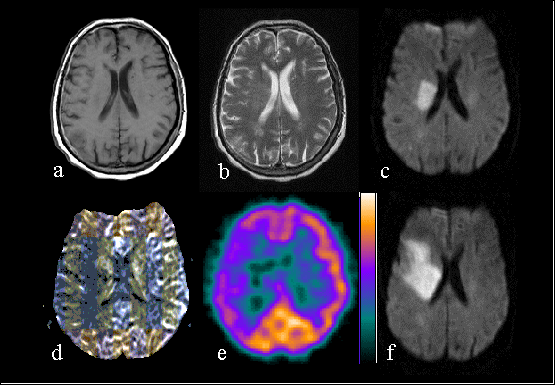

lesion volumes showed better correlation with eventual infarct volume . Figure 2 shows a representative case with

acute perfusion-diffusion mismatch and subsequent infarct enlargement. The rCBF map shows a hypoperfusion area

that is of about the same size than the perfusion defect on SPECT. In our material, the perfusion-diffusion mismatch

volume on the first day predicted worsening in early clinical outcome assessed with National Institute of Health

Stroke Scale (NIHSS) . As a conclusion, combining perfusion and diffusion imaging seems to be a particularly effective

method to assess the early hemodynamic changes in the acute ischemic stroke.

Figure 2. Seventy-three years old female with left hemiparesis. The first MRI (a-d) was performed

6.5 hours from the onset of symptoms. T1-weighted (a) and T2-weighted (b) image show very subtle findings. DWI

(C) clearly shows ischemic lesion on the right hemisphere. Map of relative cerebral blood flow (d) shows larger

perfusion defect on the right hemisphere, which is of about the same size than the perfusion defect on SPECT (e).

DWI on the next day shows the enlargement of the infarct.